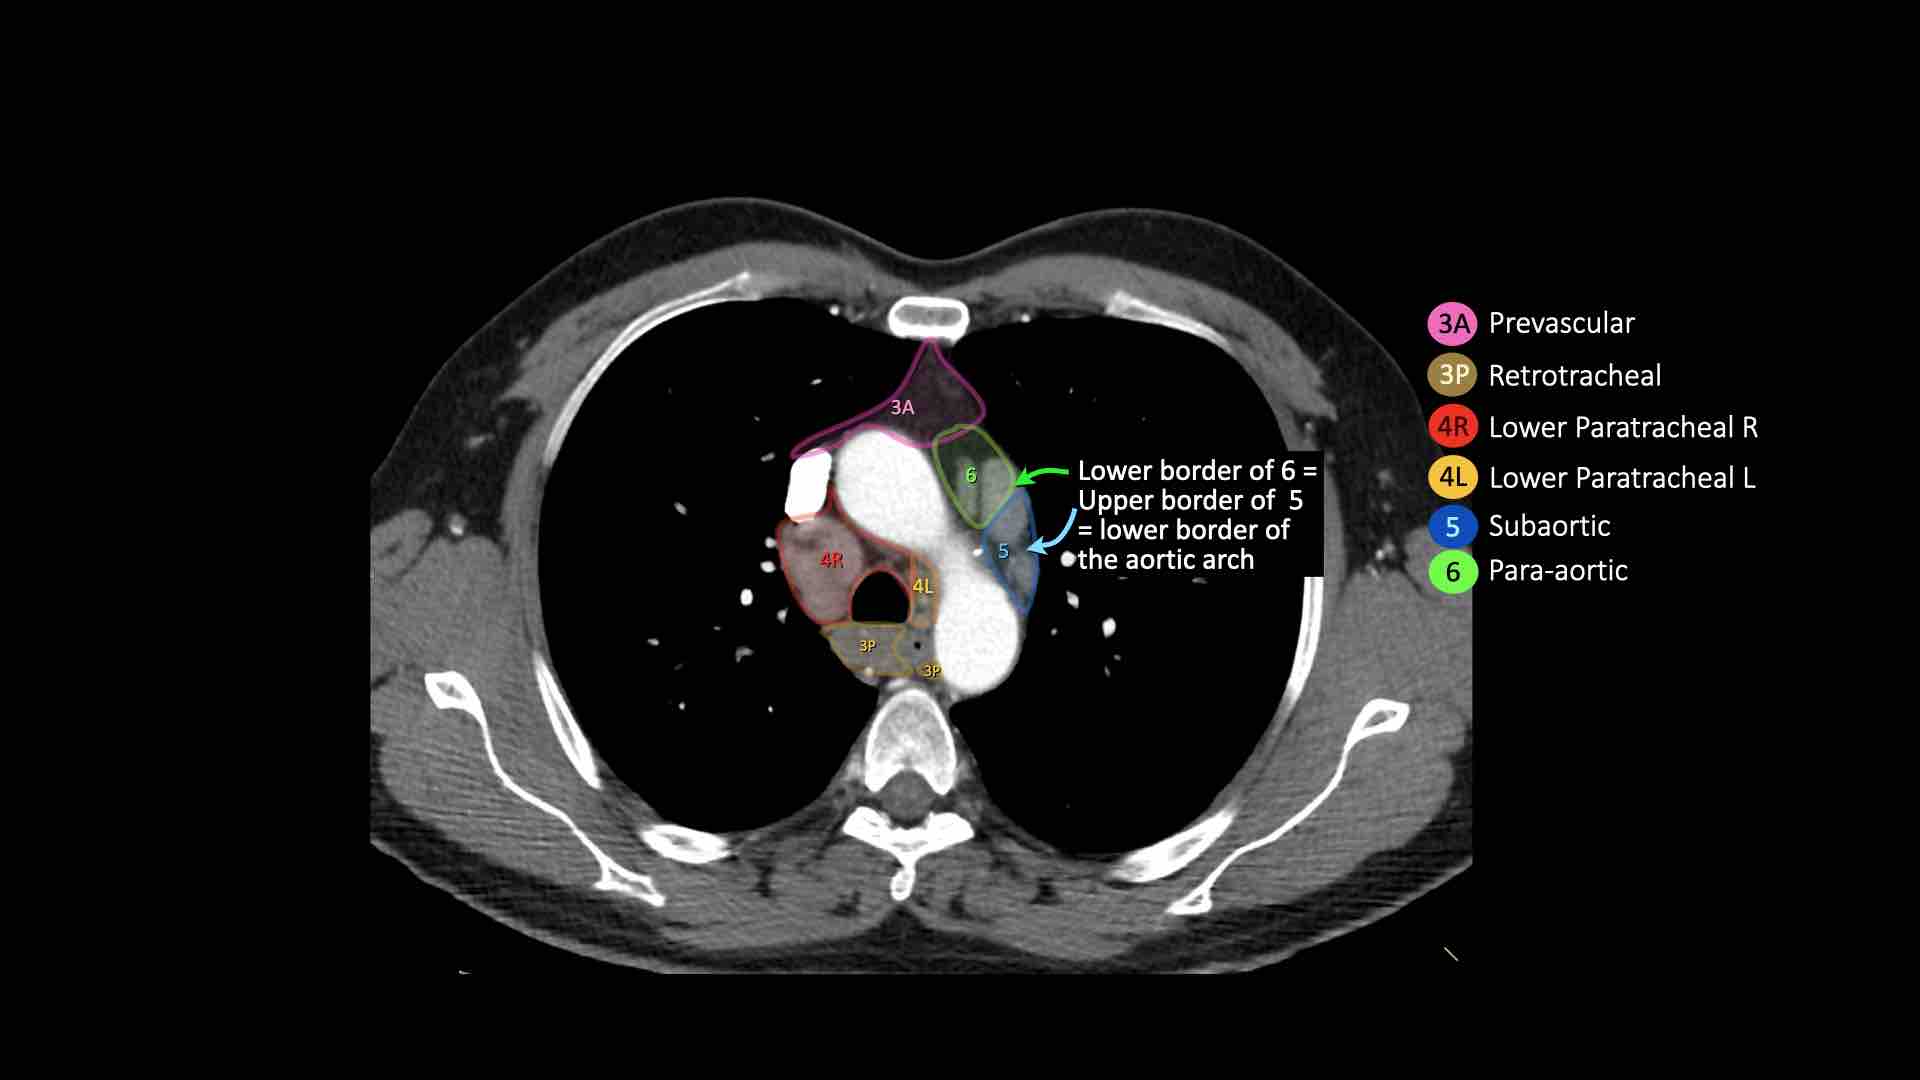

3A.Trước mạch máu

Các hạch này không tiếp giáp với khí quản như các hạch ở nhóm 2, mà nằm ở phía trước các mạch máu.

3P.Trước cột sống

Các hạch không tiếp giáp với khí quản như các hạch ở nhóm 2, mà nằm sau thực quản, tức là ở vị trí trước cột sống.

4R.Cạnh khí quản dưới

Từ điểm giao nhau giữa bờ dưới tĩnh mạch vô danh (tĩnh mạch tay đầu trái) với khí quản đến bờ dưới tĩnh mạch đơn.

Hạch nhóm 4R trải dài từ bờ bên phải đến bờ bên trái của khí quản.

4L.Cạnh khí quản dưới

Từ bờ trên của quai động mạch chủ đến bờ trên của động mạch phổi trái.

Hạch động mạch chủ nhóm 5-6

5. Dưới động mạch chủ

Các hạch này nằm trong cửa sổ phế động mạch (AP window), ở phía ngoài dây chằng động mạch.

Các hạch này không nằm giữa động mạch chủ và thân động mạch phổi mà nằm ở phía ngoài các mạch máu này.

6. Cạnh động mạch chủ

Đây là các hạch của động mạch chủ lên hoặc hạch cơ hoành, nằm ở phía trước và bên của động mạch chủ lên và quai động mạch chủ.

4L. Hạch cạnh khí quản dưới bên trái

Hạch nhóm 4L là các hạch cạnh khí quản dưới nằm bên trái bờ trái của khí quản, giữa đường nằm ngang tiếp tuyến với bờ trên quai động mạch chủ và đường tiếp tuyến với bờ trên động mạch phổi trái.

Nhóm này bao gồm các hạch cạnh khí quản nằm ở phía trong dây chằng động mạch.

Hạch nhóm 5 (cửa sổ phế động mạch) nằm ở phía ngoài dây chằng động mạch.

Bên trái là hình ảnh ngay trên mức thân động mạch phổi, cho thấy các hạch cạnh khí quản dưới bên trái và bên phải.

Ngoài ra còn có các hạch nhóm 3 và nhóm 5.

Bên trái là hình ảnh ở mức phần dưới khí quản, ngay trên carina.

Bên trái khí quản là các hạch 4L.

Lưu ý rằng các hạch 4L này nằm giữa thân động mạch phổi và động mạch chủ, nhưng không nằm trong cửa sổ phế động mạch, vì chúng nằm ở phía trong dây chằng động mạch.

Hạch nằm bên ngoài thân động mạch phổi là hạch nhóm 5.

5. Hạch dưới động mạch chủ

Hạch dưới động mạch chủ hay hạch cửa sổ phế động mạch nằm ở phía ngoài dây chằng động mạch hoặc động mạch chủ hoặc động mạch phổi trái, ở đoạn gần trước nhánh đầu tiên của động mạch phổi trái, và nằm trong bao màng phổi trung thất.

6. Hạch cạnh động mạch chủ

Hạch cạnh động mạch chủ (động mạch chủ lên hoặc cơ hoành) nằm ở phía trước và bên ngoài động mạch chủ lên và quai động mạch chủ, từ bờ trên đến bờ dưới của quai động mạch chủ.